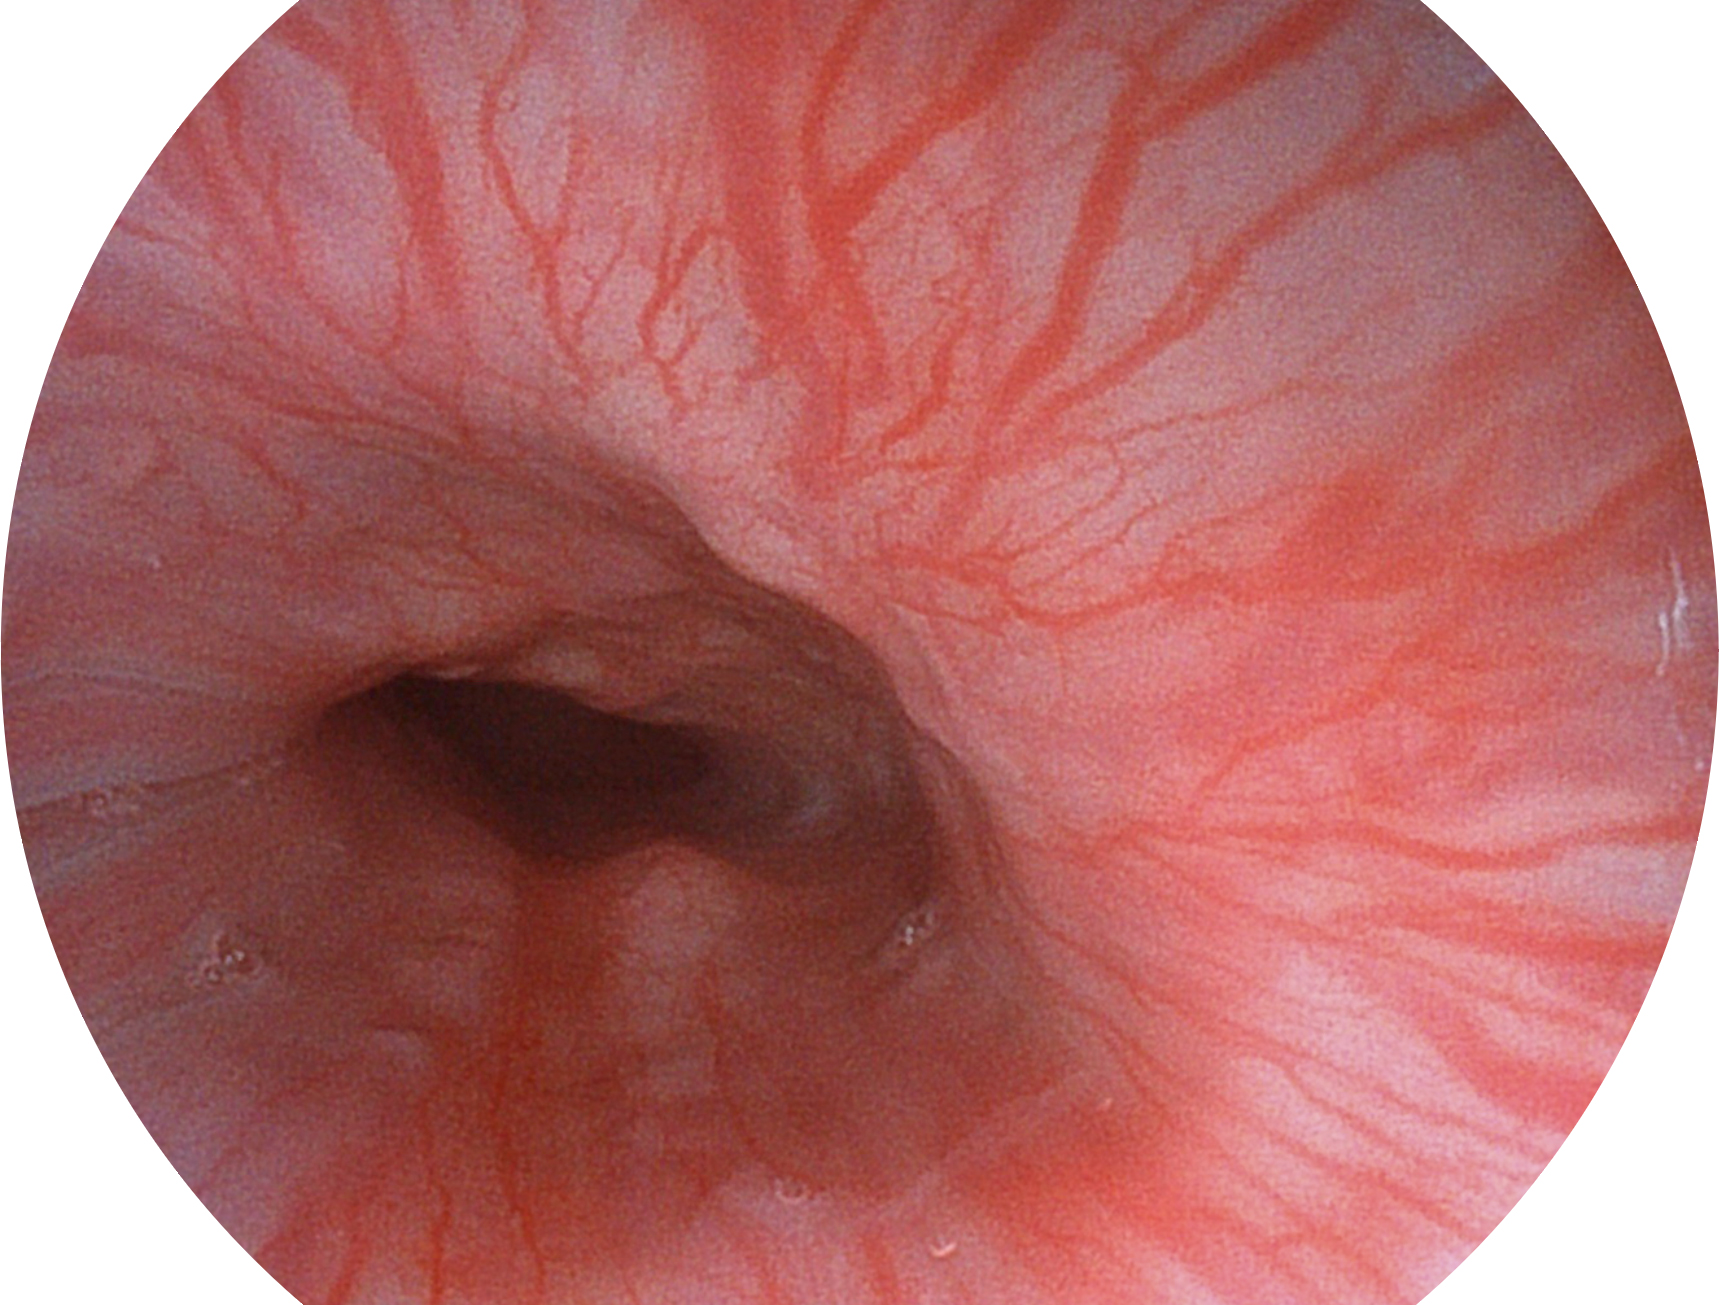

玖鼎集团新开发的内镜染色技术,主要是基于多波长LED 光源的开发,VLS-55Q 四波长LED 光源是由四个不同颜色的LED光按照相应照明模式所规定的特定发光比例进行合束后形成,合束后形成的照明光的光谱由红光、绿光、蓝光及蓝紫光这四个不同的波段范围构成。具有更高光谱自由度,通过光谱比例的控制,实现了聚谱成像技术,英文全称为“Spectral Focused Imaging, SFI”,缩写为“SFI”和光电复合染色成像技术,英文全称为“Versatile Intelligent Staining Technology, VIST”,缩写为“VIST”。